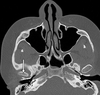

right uncinate process

33